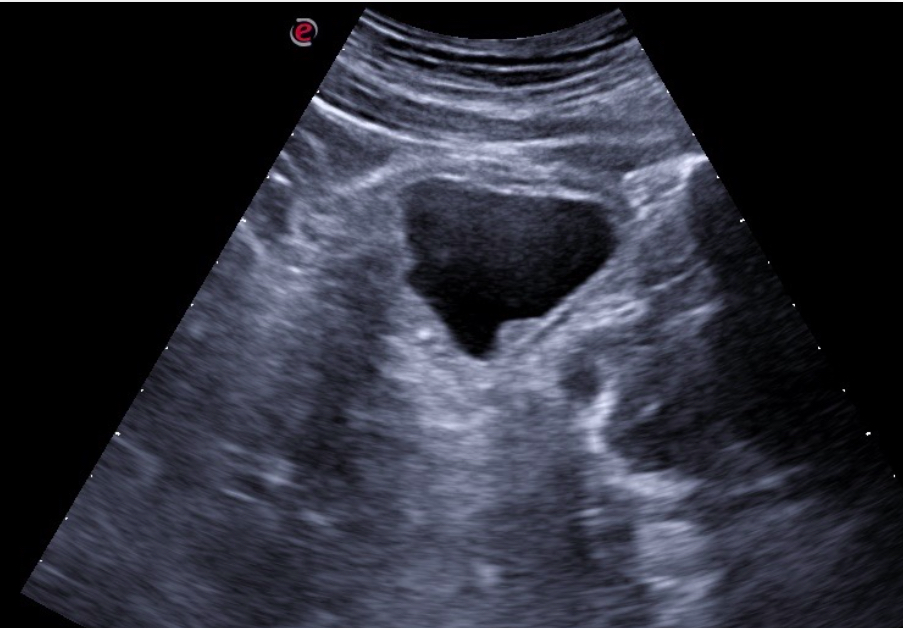

Expondremos la utilidad de la EC como herramienta en el manejo de los pacientes con diferentes tipos de dolor que atiende el Médico de Familia en las consultas diarias, urgentes, e incluso en los domicilios, en diversos escenarios clínicos a los que podemos enfrentarnos en nuestra práctica clínica habitual, desde un dolor visceral (abdominal, torácico, urológico o ginecológico), un dolor músculo-esquelético (traumático o no, con sospecha de fractura u osteoartrósico incapacitante), un dolor vascular (sospecha de trombosis venosa profunda, trombosis arterial aguda, aneurismático); ayudando a obtener una información crucial con un método no invasivo que nos ayudará a reducir la incertidumbre y orientar mejor el diagnóstico de nuestros pacientes e incluso nos podrá ser muy útil como herramienta con fines terapéuticos como en el caso de las infiltraciones ecoguiadas.

En nuestra experiencia como Centro de Salud que utiliza de forma rutinaria la Ecografía clínica, hemos visto un importante avance en nuestra capacidad resolutiva en muchos casos, mejorando el diagnóstico diferencial de los diferentes tipos de dolor, su abordaje terapéutico precoz, e incluso ayudando a los pacientes a una mejor comprensión de su patología.

Consideramos la Ecografía clínica como una herramienta de gran utilidad en la consulta de Atención Primaria, que puede aportar gran ayuda al Médico de Familia en la toma de decisiones, ayudando a obtener diagnósticos diferenciales precoces y que también ayuda a agilizar las derivaciones pertinentes al conseguir en muchos casos un enfoque diagnóstico más preciso.